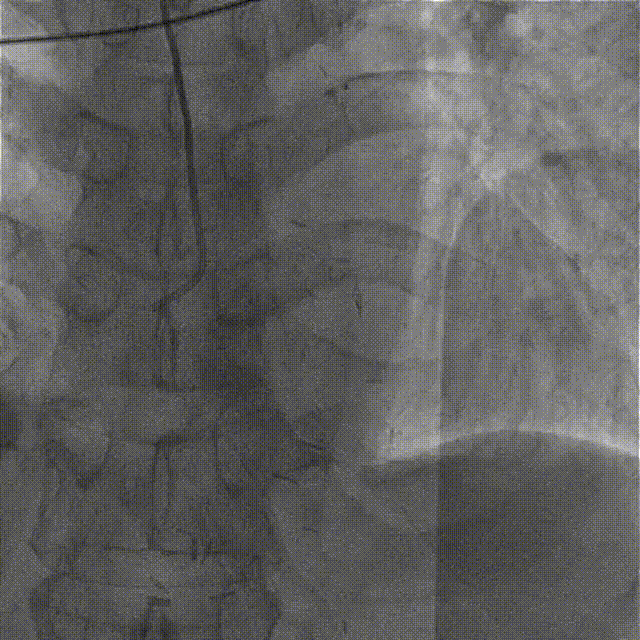

冠脉造影结果

LCA:

· LM:(-);

· LAD:无残端闭塞(CTO病变),TIMI血流0级;

· LCX:全程管壁不规则,OM1远段经心外膜向前降支提供侧枝,TIMI血流Ⅲ级。

RCA:右冠近段管壁不规则,远段经心外膜向LAD提供侧枝循环。

桥血管造影:LIMA-LAD桥血管完全闭塞。

置7F UBS 3.75、6F JR 4.0指引导管至左右冠开口,分别送入Marvel导丝至LCX远段、RCA远端加强支撑,行双侧造影。